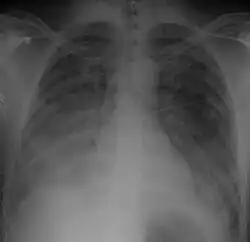

| Chest Xray of a 40 yr old male in acute respiratory distress syndrome as a complication of murine typhus | |